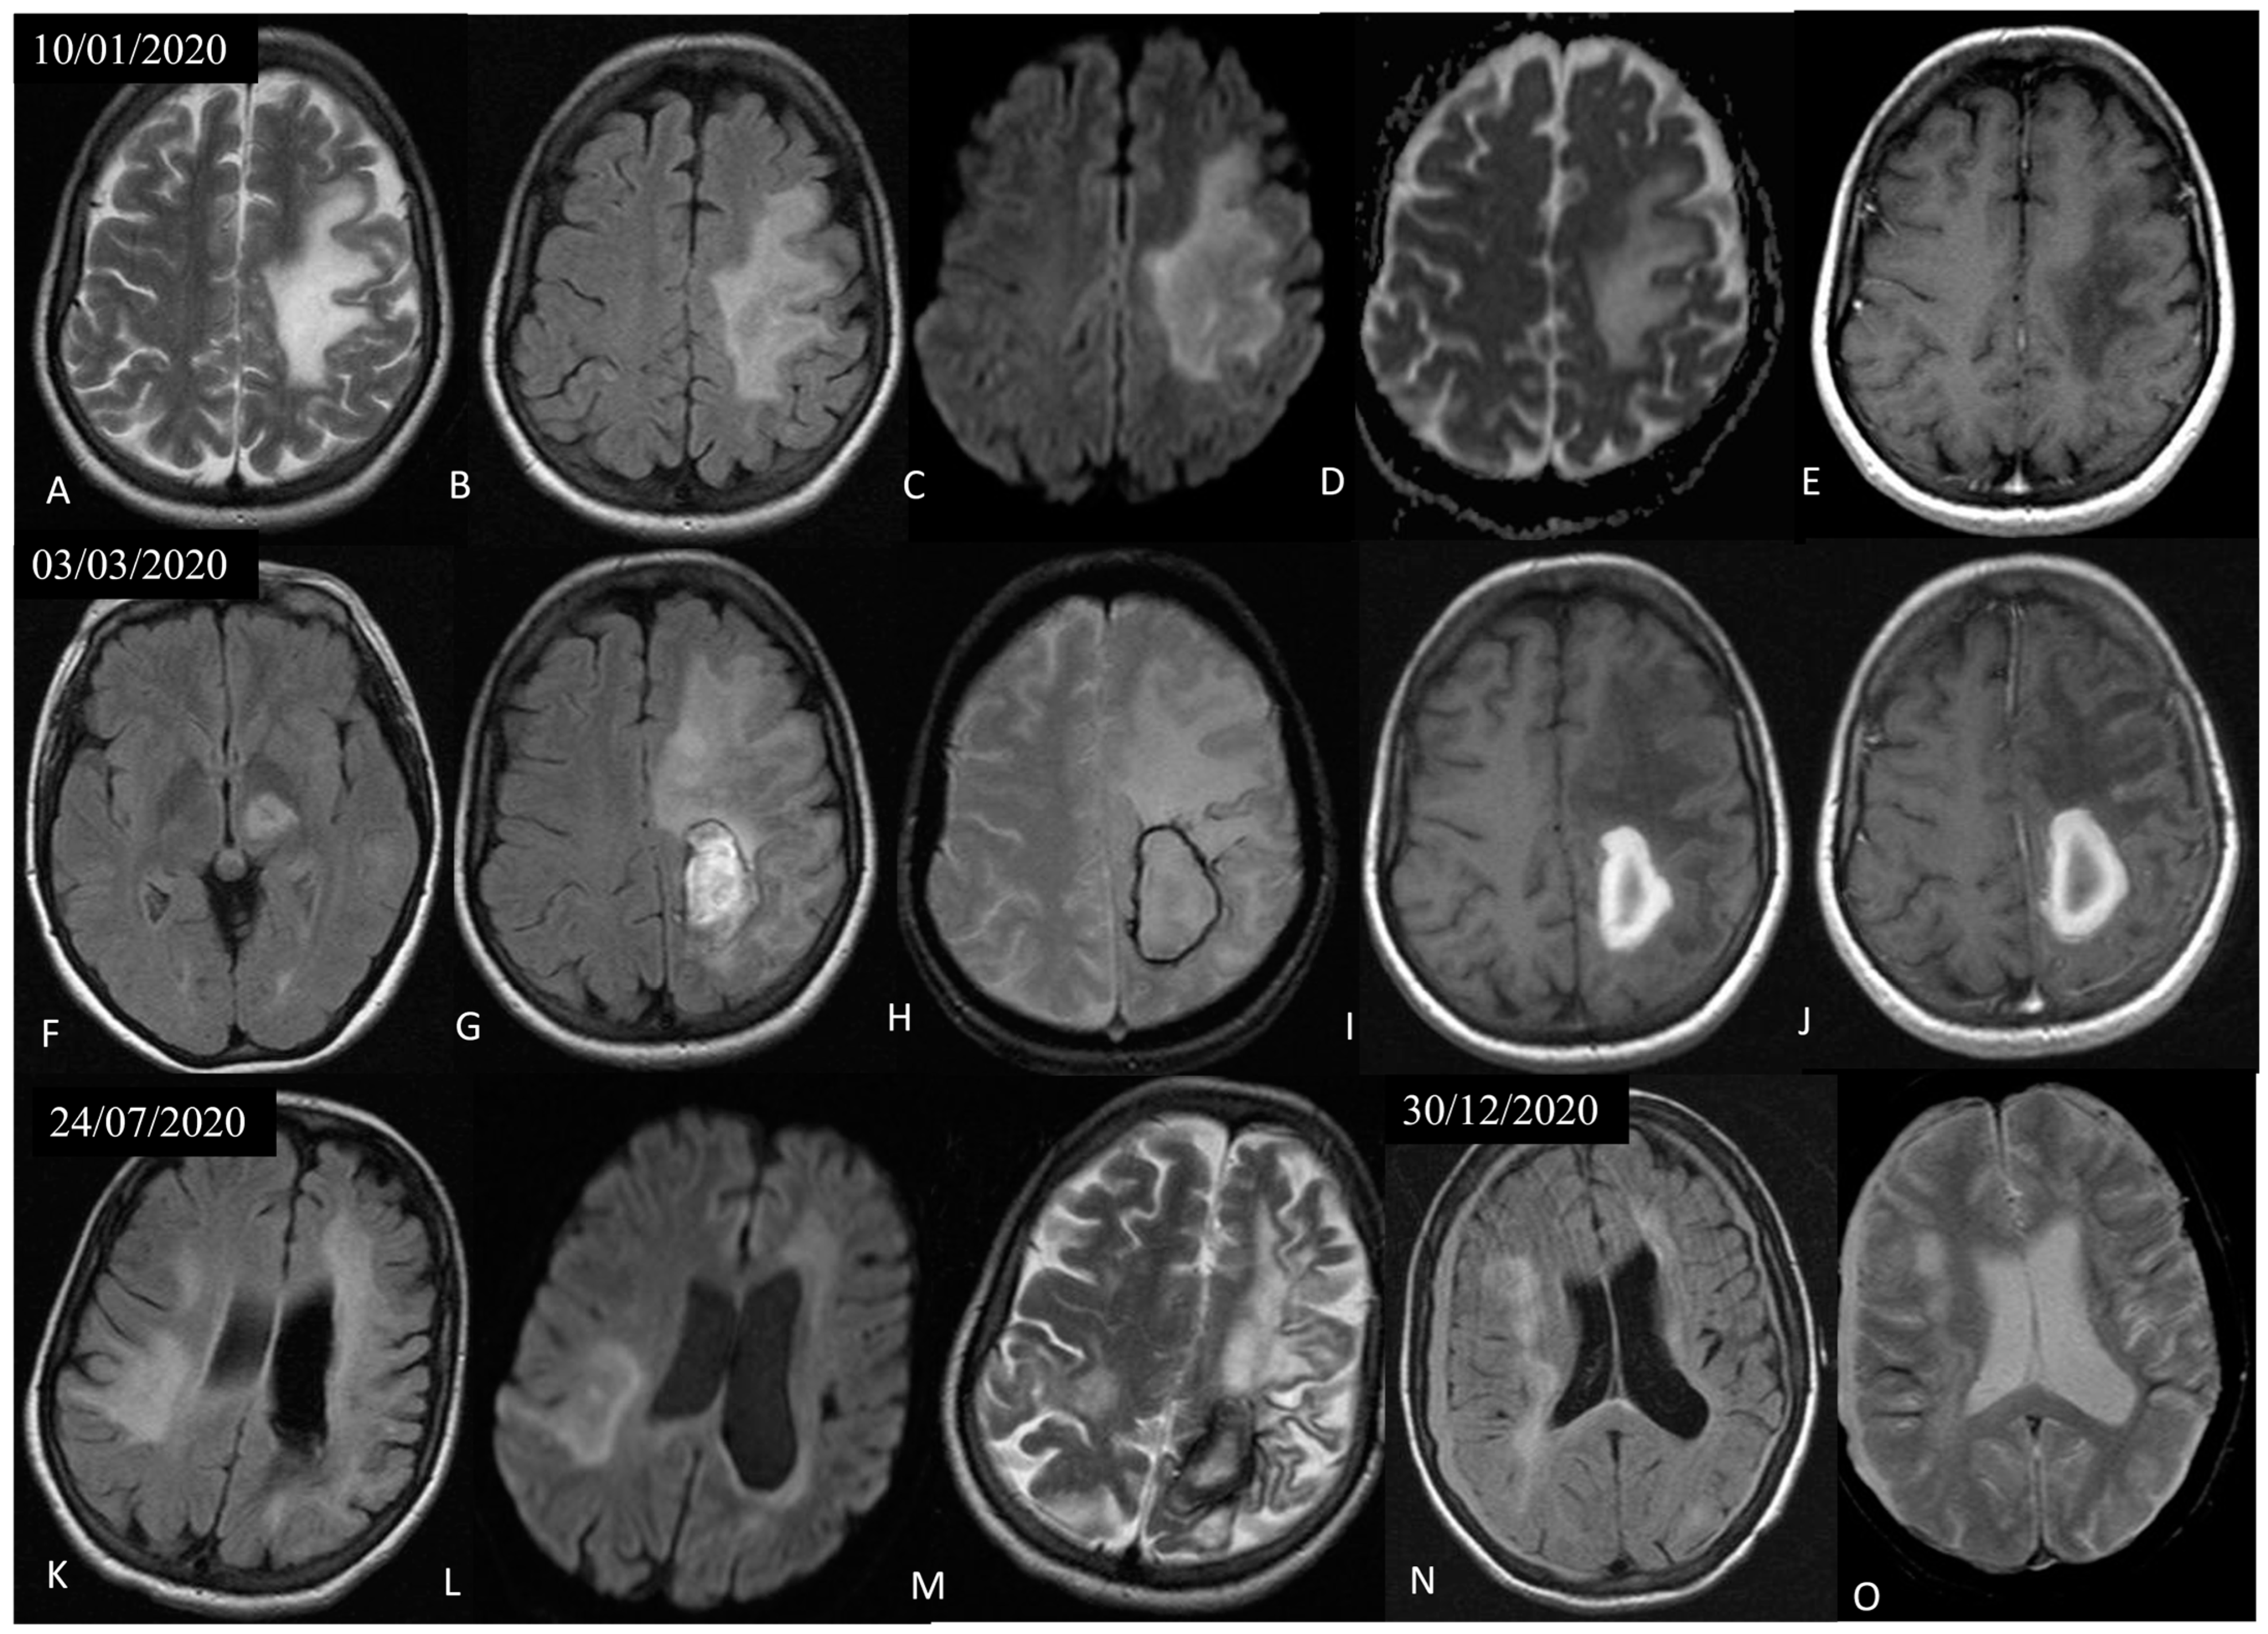

Soon after, the patient deteriorated with new-onset dysarthria and mixed aphasia. A new brain MRI showed expansion of the non-enhancing, white matter, T2 hyperintense lesions in the left frontoparietal area, with characteristic involvement of the U-fibers, lack of mass effect, and peripheral restricted diffusion, findings that raised high suspicion for PML (Figure 3). At this point, a second lumbar puncture was performed, in which PCR for JCV in the CSF was positive. Nonetheless, the lack of heavy treatment-related immunosuppression prompted us to perform a brain biopsy in order to exclude other pathologies such as lymphoma. Histological examination demonstrated extensive demyelination with macrophage-rich lesions (CD163+ foam-like cells) and oligodendroglia with enlarged, glassy nuclei, suggestive of polyoma virus infection [14].

The patient continued to deteriorate with the appearance of global aphasia and left-sided hemiparesis. New brain MRIs showed progression of the pre-existing left frontoparietal lesion; new lesions in the left thalamus, extending to the mesencephalon and also to the right frontotemporal and parietal areas, with imaging characteristics suggestive of PML; further loss of brain parenchyma and cortical hemorrhagic deposition in the left hemisphere; as well as an intraparenchymal hematoma in the left parietal lobe and bilateral subdural hematomas (Figure 3). In the ensuring months, she was hospitalized multiple times due to recurrent episodes of aspiration pneumonia. Along with the neurologic decline, she gradually developed severe pancytopenia attributable to SLE, and as a rescue therapy, she received intravenous immune globulin (IVIG). However, her clinical status progressed and she eventually died 15 months after the diagnosis of PML.

Figure 3. Axial T2 (A), FLAIR (B), DWI (C), ADC map (D), and post-Gadolinium T1 (E) sections of a follow-up brain MRI that was performed 1,5 months after the initial MRI, showed expansion of the pre-existing non-enhancing, T2 hyperintense, white matter lesion in the left frontoparietal area, with characteristic involvement of the U-fibers, lack of mass effect, and peripheral restricted diffusion, indicative of PML. Two months later, axial FLAIR (F,G), GRE (H), and pre- (I) and post-Gadolinium T1 (J) sections of a follow-up MRI showed further progression of the non-enhancing left frontoparietal lesion, a new lesion in the left thalamus, extending to the mesencephalon, and a subacute left parietal hematoma. Two more follow-up MRIs 5 months (axial FLAIR (K,L) and T2 (M)) and 10 months (axial FLAIR (N) and GRE (O)) later revealed new lesions in the right frontotemporal and parietal areas, with imaging characteristics also suggestive of PML, further loss of brain parenchyma and cortical hemorrhagic deposition in the left hemisphere, as well as bilateral frontoparietal subdural hematomas.